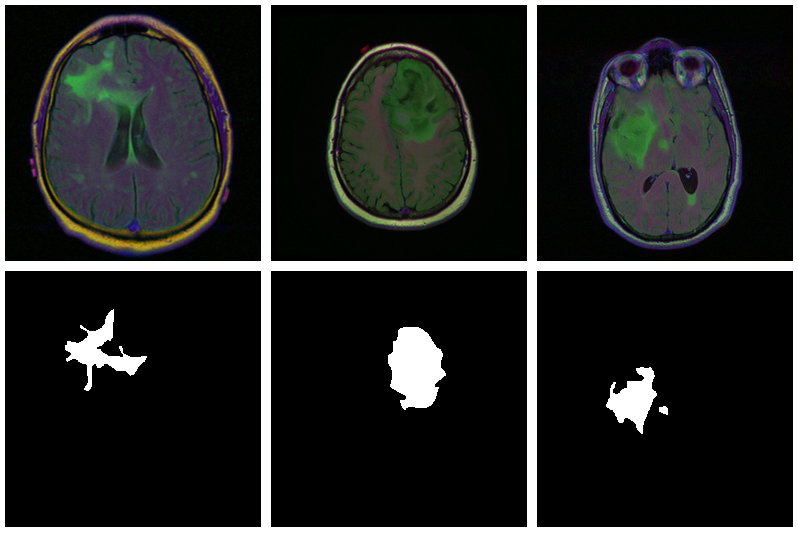

With U-Net, domain applicability is as broad as the architecture is flexible. Here, we want to detect abnormalities in brain scans. The dataset, used in Buda, Saha, and Mazurowski (2019), contains MRI images together with manually created FLAIR abnormality segmentation masks. It is available on Kaggle.

As is often the case in medical imaging, there is notable class imbalance in the data. For every patient, sections have been taken at multiple positions. (Number of sections per patient varies.) Most sections do not exhibit any lesions; the corresponding masks are colored black everywhere.

Here are three examples where the masks do indicate abnormalities:

Let’s see if we can build a U-Net that generates such masks for us.